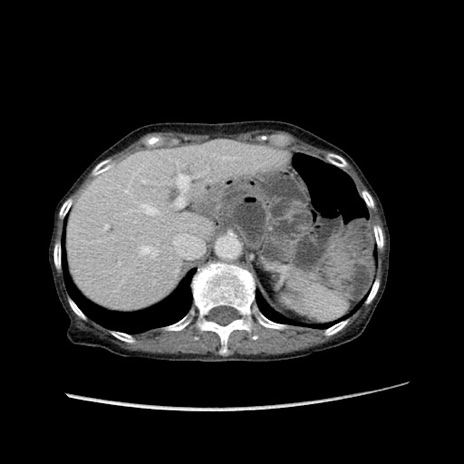

症例25(横断像)

【症例】80歳代女性

【主訴】胸のつかえ感

【現病歴】約9時間前に食後から胸のつかえた感じあり、嘔吐あり、来院。

【既往歴】胃癌(全摘)、胆摘、虫垂炎

【身体所見】心窩部に圧痛あり、反跳痛なし。

【データ】WBC 5700、CRP 0.05